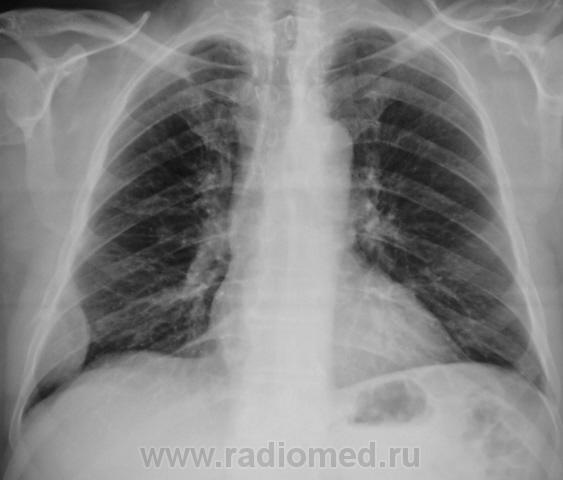

Контроль после флюолрографии.  Мезотелиома или что-то другое?

А не м.б. осумкованный плеврит? Хотя м.б. и мезотелиома ....- сомнения может разрешить КТ

Скорее деструкция 6 ребра с мягкотканным компонентом

Да, деструкция ребра видна хорошо, да и сиротские фрагменты (костные) тоже. "Мягкотканный компонент", прямо богатейший.

Мезателиома отпадает, данную картину мы бы не увидели за счет жидкости плевральной полости, а вот саркому Юинга бокового отрезка ребра я бы предположил.

Может и Юинг, хотя мне кажется староват, а может: мтс, плазмоцитома, хондросаркома и т.д. В смысле, и все остальные опухоли костей. Потому надо брать биопсию, благо, в этом месте не сложно.

Томограммы не делали. По прямому снимку стало ясно все, по крайней мере  - онкология. Пациента сразу же направили ООД. Татьяна Валентиновна права - биопсия решит все, да, и взять не трудно.

На мой взгляд Вы правы. По всей видимости, в данном случае, что-то типа саркомы Юинга или рядом.

Ограниченая форма мезотелиомы вполне соответствует этой картине (и форма пристеночного затемнения, и его края, и деструкция ребра - трудно представить что либо иное...даже метастаз в ребро вряд ли сопровождался бы таким мягкотканным компонентом). И если честно - встречались. Конечно, по понятным причинам, сейчас продемонстрировать подтверждение не могу - цифровых снимков тогда не было...увы. И не факт, что через месяц там не будет жидкости до уровня первого ребра.....